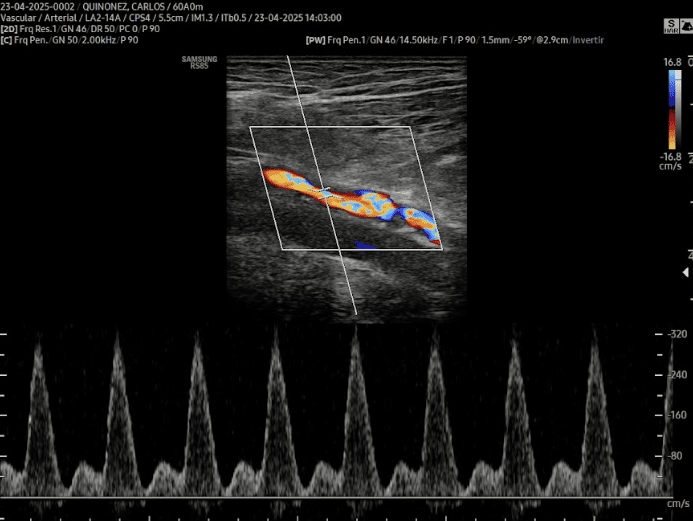

ECOGRAFÍAS DE 2DA OPINIÓN Hígado Tiroides Mama Venoso Arterial Carotideo Partes Blandas Urológica - Pene Hígado Trasplantado Riñón Trasplantado

ECOGRAFÍAS Tiroides Abdomen Urológica Vascular Pediatría-Neonatal Músculo Esquelético Obstetricia 4D - 5D Ginecología Partes Blandas